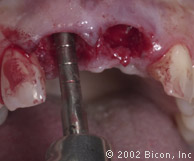

Подготовка к установке постоянной конструкции

Произведены послабляющие разрезы

Установка готовых конструкций